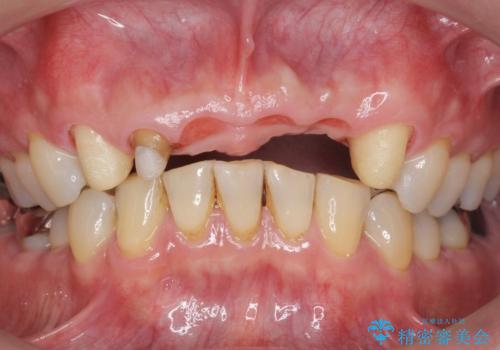

- お風呂場で転んで上の前歯が2本抜けてしまったことを主訴に来院された患者様です。

精査したところ、左上の側切歯(左上2)も破折しており保存不可能な状態でした。

左上の側切歯(左上2)を抜去し、右上の側切歯(右上2)の再根管治療後、セラミックのブリッジによる補綴を行いました。